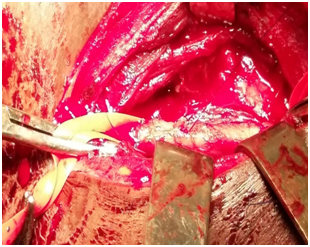

Case 1: A 40-year-old man, with no previous medical history, consulted for high dysphagia, a fever. The notion of fish bone ingestion, evolving for 5days was found. Clinical examination revealed an inflammation on the posterior wall of the oropharynx. A cervical x-ray and a CT-Scan showed the foreign body (Figure 1). Endoscopy did not found the foreign body Surgical exploration (Figure 2) allowed the drainage of the abscess, and extraction of the fish bone. Parenteral antibiotic was administrated. After 45days, patient was reviewed without particularity.

Figure 2 Intraoperative picture of the removal of the foreign body. The drainage of the abscess and extraction of the bone fish.